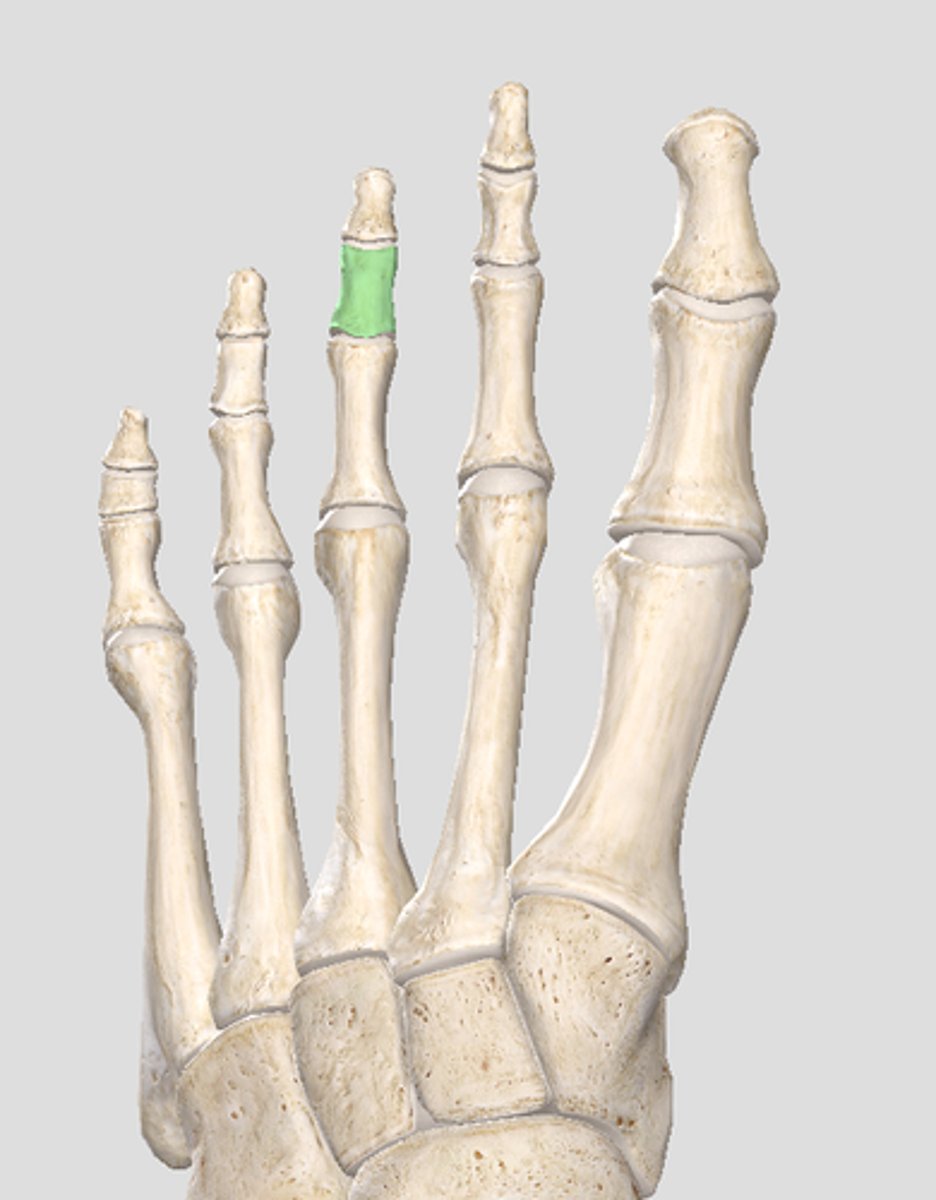

Middle phalanx of digit 3

Distal phalanx of digit 3